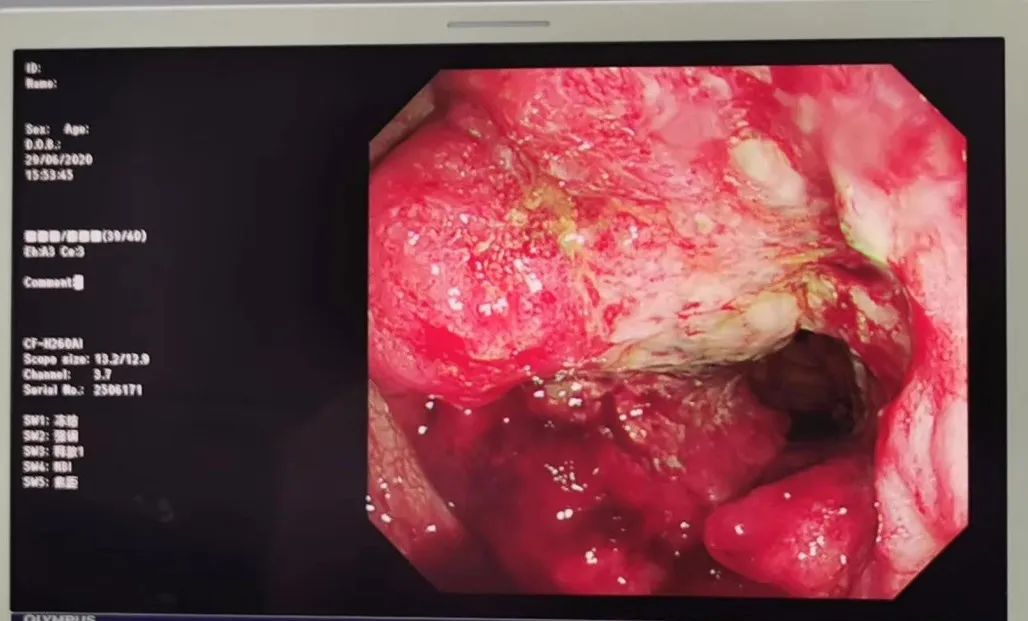

妙手医院张洁院长为唐大爷做了直肠指检,在直肠距肛门约5cm处摸到了一大小约4*5cm质地较硬的肿物,于是又为他安排了肠镜检查,这一查,结果让唐大爷大吃一惊。肠镜显示,他的直肠上确实有一个不小的肿块,在活检后,最终被确诊为直肠癌。

果不其然,胃肠镜检查发现,在直肠和乙状结肠交界处,有一环周样巨大病灶,这哪里是痔疮啊,分明是进展期肠癌!

患者在这次来诊前,出现便血已经2年多了,反复多次以“痔”诊疗,痔疮膏涂抹过,中西药都吃过,就是没想到去医院看看。直到现在,他还以为是痔疮。像这种情况,至少是进展期,只有外科手术了,具体分期还需要等待病理和免疫组化,预后也难以预料。